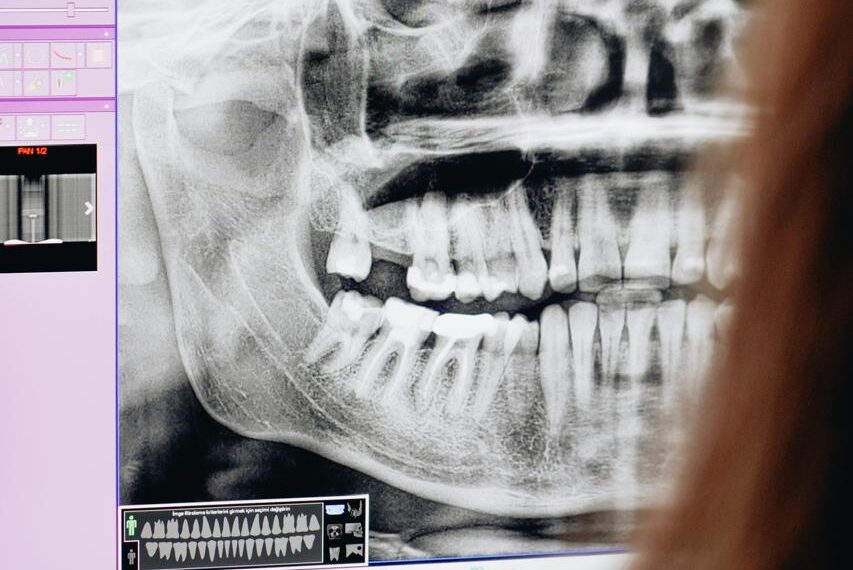

Muelas del juicio provocan dolor en 80% de la población mexicana

Cerca del 80% de los mexicanos padecen dolor debido a la aparición de las muelas del juicio, que puede acompañarse de problemas al masticar, presión en los otros dientes, inflamación, caries, e irritación, señaló el cirujano oral y maxilofacial Carlos Contreras Castellanos.

“Las muelas del juicio son una de las principales causas de visitas al dentista y con frecuencia  pueden requerir extracción inmediata o tratamiento debido a las complicaciones que puedan presentarse. “Es importante revisar al paciente para evaluar la situación y saber si los terceros molares son la causa del problema”, dijo el especialista.

De acuerdo al doctor Contreras, el ser humano cuenta con 32 piezas dentales, incluyendo las cuatro muelas del juicio, sin embargo, debido a algunos procesos evolutivos la mandíbula y el maxilar han disminuido su tamaño afectando con ello a un espacio suficiente para los terceros molares y/o para el apiñamiento o malposición dental.

Destacó que las muelas del juicio comienzan su erupción alrededor de los 17 y hasta los 25 años en promedio y que se debe valorar e individualizar cada caso para determinar si es necesaria o no la extracción.  En algunos casos solo erupcionan tres muelas y en otros ninguna.

Es importante valorar al paciente con una evaluación clínica y radiográfica para determinar el estado y posición de las mueles del juicio, posteriormente se realizará el proceso de extracción con anestesia local o sedación para que el paciente no tenga dolor.